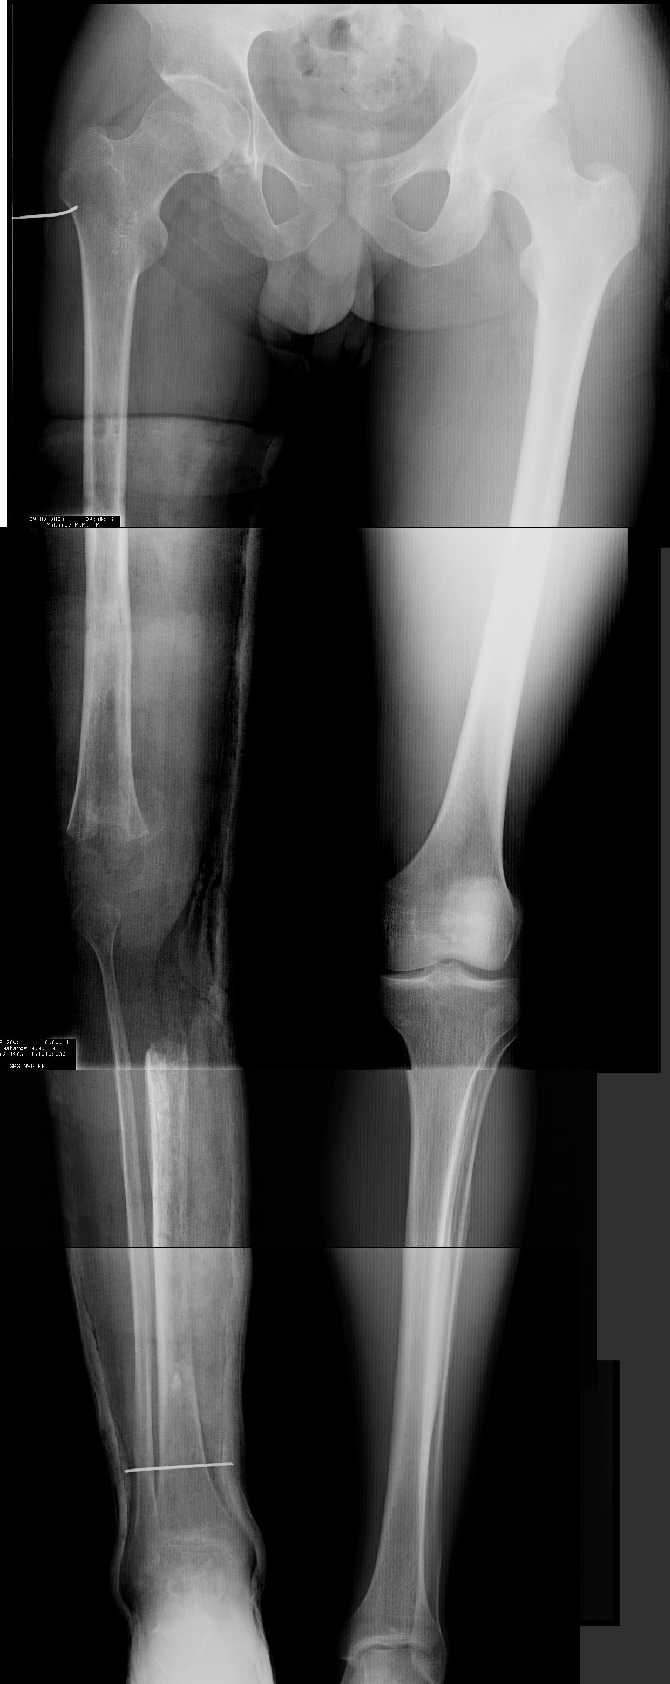

Женщина, 29 лет.В 2001 году получила политравму (таз, открытый многооскольчатый перелом правой бедренной кости на границе средней и нижней трети со смещением,

открытый перелом правой голени, пятки, закрытый - правого надколенника, поперечного отростка L4, пальцев кисти, сотрясение головного мозга).

Переломы конечностей лечились АВФ.В настоящее время стойкая разгибательная контрактура правого коленного сустава (сгибание 105-110 гр., разгибание 160-165 гр.), варусная деформация, болевой синдром.

Даже по этим коротким снимкам видно, что варусная деформация на уровне бедра. Хотя для полноценной оценки оси сделать надо снимок всей конечности, от таза до стопы. Наклеить метки на кожу, по которым сделать склейку. И профиль бы тоже неплохо посмотреть.

Уважаемый Антон, при определении уровня остеотомии и величины коррекции руководствуемся, обычно, необходимостью обеспечить нормаль механической оси к середине опорной поверхности большеберцовой кости. Расчет производится по рентгенограмме (рентгенограммам) конечности под нагрузкой, которые визуализируют положение головки бедренной кости относительно таранной кости. На представленных рентгенограммах определить эти реперные точки (и заслужить Вашу зараннюю благодарность) не представляется возможным. Остается неясным с каким исходом сросся перелом правой большеберцовой кости. Складывается впечатление, что нанесены не механические, а анатомические оси. Исправлять проще за счет "минус - кость", но механически правильнее "плюс". Чтобы выполнить механические требования, иногда на ряду с угловой коррекцией (деваризация-экстензия, т.к. имеется не только разгибательная, но и сгибательная контрактура)необходимо медиолатеральное смещение.

Уважаемый Антон, видимо перелом большеберцовой кости на механическую ось не повлиял, но явно варусная деформация усугубляется повреждением наружного связочного аппарата (МКС.... Просится поднагрузочный R-снимок конечности и корригировать, на мой взгляд, надо бедро (+ остеотомия, если планируется мобилизация коленного сустава).